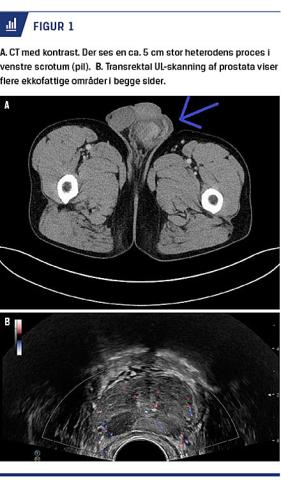

En 52-årig danskfødt mand, som tidligere havde haft et alkoholoverforbrug, fik pga. et røntgenverificeret infiltrat på højre lunge foretaget CT af thorax og abdomen. Der sås en tumorsuspekt proces i venstre scrotum og en tumorsuspekt forandring i relation til venstre vesicula seminalis (Figur 1A). Desuden sås der metastasesuspekte infiltrater i lungerne. På grund af dette blev han henvist til udredning i urologisk regi under mistanke om cancer testis.

Han havde i de seneste par måneder inden henvisningen haft udtalt nattesved og følt, at der var en hævelse af venstre scrotum. Han havde ikke følt nogen smerte, og tumormarkørerne, inklusive måling af alfaføtoproteinniveauet, var negative. En UL-skanning af scrotum viste en stor solid proces i venstre testikel. En transrektal UL-skanning (TRUS) viste suspekte forandringer i prostata og en suspekt proces i relation til venstre vesicula seminalis (Figur 1B). Der blev taget biopsier fra prostata og vesicula seminalis, og efterfølgende blev der udført operativ eksploration af venstre testikel. Der blev aspireret 70 ml strågul væske fra et hydrocele